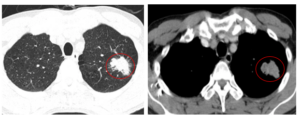

Ca lâm sàng Bệnh nhân mắc hai ung thư nguyên phát: Ung thư phổi không tế bào nhỏ và Ung thư trực tràng

Ca lâm sàng Bệnh nhân mắc hai ung thư nguyên phát: Ung thư phổi không tế bào nhỏ và Ung thư trực tràng GS.TS. Mai Trọng Khoa, PGS.TS.Phạm Cẩm Phương, BSCKII. Lê Viết Nam, BSNT. Nguyễn Bảo Linh Trung tâm Y học hạt nhân và Ung bướu, Bệnh viện Bạch Mai Mở...